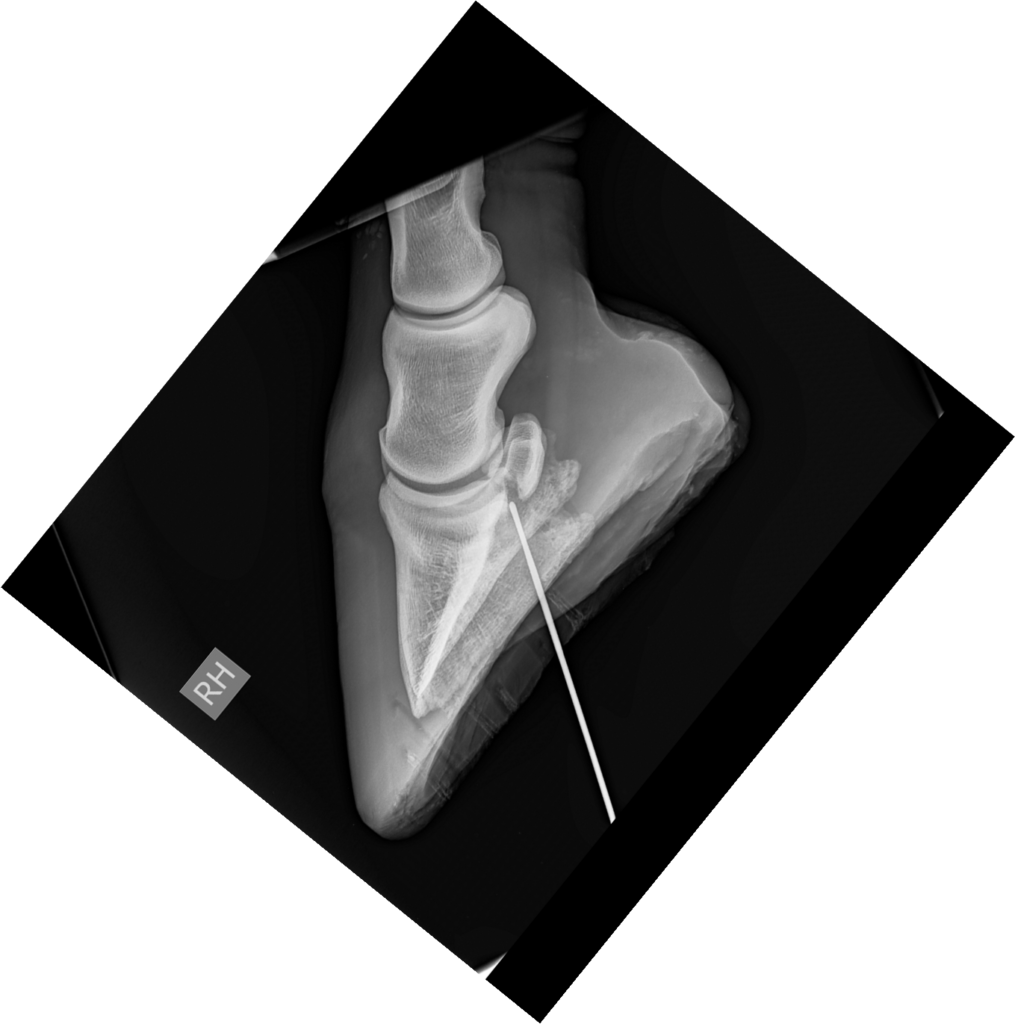

Er werden vervolgens radiografieën (LM; DPr-PlDiO) met metalen sonde genomen. Welke anatomische structuren zijn mogelijks betrokken?

LM (op podoblock)

De metalen sonde heeft een proximoplantaire richting en eindigt ter hoogte van het plantaroproximaal aspect van het hoefbeen en distaal van de distale rand van het straalbeen.

Anatomische structuren welke hoogstwaarschijnlijk betrokken zijn bij deze nageltred zijn: de diepe buigpees, lig. sesamoideum distale impar, de bursa podotrochlearis en de plantarodistale recessus van het hoefgewricht.

Geen bot afwijkingen vastgesteld.